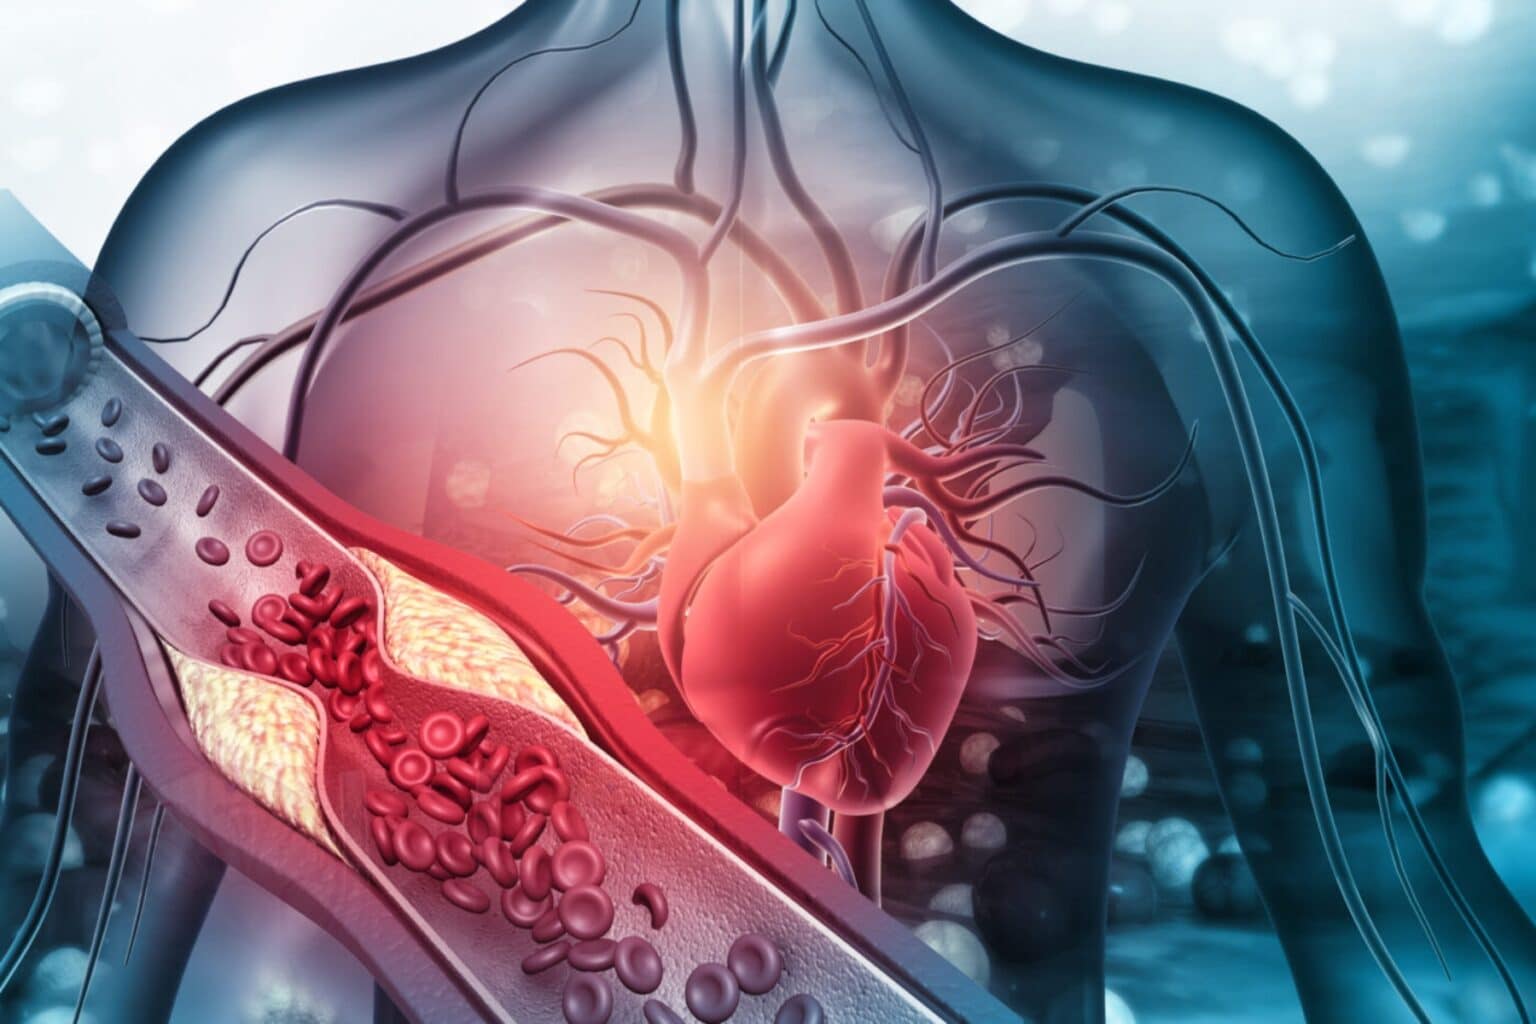

Ο καιρός είναι ένας άλλος ένοχος όταν πρόκειται για χειμερινά καρδιακά προβλήματα. «Όταν αναπνέουμε κρύο αέρα, παγώνει το αίμα στους πνεύμονές μας και προκαλεί συστολή των αιμοφόρων αγγείων», είπε ο Lloyd-Jones. «Τα πρώτα αιμοφόρα αγγεία προς τα κάτω από τους πνεύμονες είναι οι στεφανιαίες αρτηρίες, οι οποίες επηρεάζονται ιδιαίτερα από το κρύο. Η επιδίωξη δραστηριοτήτων σε κρύο καιρό, όπως το φτυάρι, μπορεί να είναι ιδιαίτερα επικίνδυνη επειδή μπορεί να το παρακάνουμε, καθώς και να φοράμε επιπλέον ρούχα, τα οποία θα μπορούσαν να μας προκαλέσουν υπερθέρμανση».

Τα κλασικά συμπτώματα καρδιακής προσβολής στους άνδρες είναι βαριά, συντριπτική πίεση στη μέση του θώρακα ή ξαφνική, ανεξήγητη δύσπνοια. Τα συμπτώματα για τις γυναίκες μπορεί να είναι τα ίδια ή πιο διάχυτα, όπως μόνο δύσπνοια ή έντονη κόπωση ή περιστασιακά ζάλη και ζαλάδα.